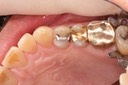

Alan Chinn #28 prep